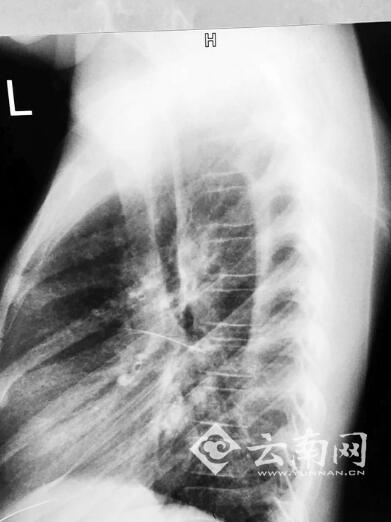

经过急救科详细诊断,可以确诊钢针从胸腔剑突下向上斜刺入小甜心房。更为严重的是钢针已经断成两截,针头部分直刺入右心房,针尾一截留在皮肤与胸膜间。专家分析后认为,是心脏巨大的收缩和扩张力量,硬生生将钢针折断。

经过专家会诊后,决定先由胸外科将胸膜里的针尾取出,再由心外科组织手术将刺入右心房的针头取出。

据心外科主任庞中一介绍,当时情况非常危急,因为针头刺破部分心血管,小甜心房内已经积压大量淤血,随时可能因“心房填塞”而猝死。

手术由庞中一主任亲自主刀,经过一个小时的救治,刺入小甜心房的针头被顺利取出,积压心房的淤血全部清理干净。